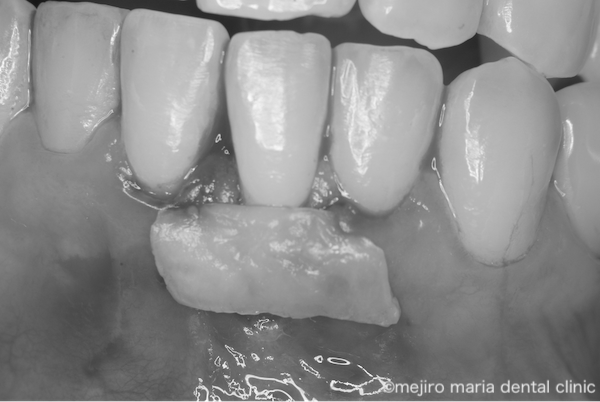

そのため、口蓋(上顎)の歯茎(結合組織)を採取し、下がった歯茎の部位に移植する「結合組織移植術」と、両側の歯茎を引き寄せるように縫合を行う「根面被覆術」を併用し、露出した歯根を被覆する治療のみを実施しました。

【結合組織移植術】

ご自身の口蓋の歯茎(結合組織)を採取し、下がった歯茎を覆うように歯茎の中に移植する治療法

【根面被覆術】

歯茎が下がってしまった部分について、両側の歯茎を引き寄せるように縫合を行うことで露出した歯根を被覆する方法